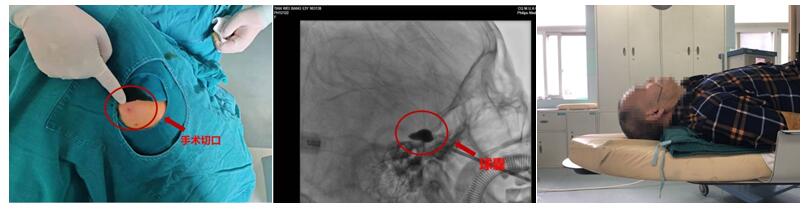

病例1 难治性性三叉神经痛的微创治疗:微球囊压迫术术中球囊成形

三叉神经痛(Trigeminal Neuralgia, TN) 是最常见的颅神经疾病,其发病率为52.2/10万,表现为一侧面部三叉神经分布区内反复发作的阵发性剧烈痛,特点是:发病骤发、骤停,呈闪电样、刀割样、烧灼样、顽固性、难以忍受的剧烈性疼痛。说话、洗脸、刷牙都会导致阵发性的剧烈疼痛。疼痛历时数秒或数分钟,发作间歇期同正常人一样。自2000年起,神经外科相继开展了三叉神经半月结甘油和射频热凝术治疗原发性三叉神经痛,成为重庆市最早、持续时间最长开展原发性三叉神经痛微创治疗的单位之一。2017年陈维福教授率先在西部地区开展微球囊压迫术治疗难治性性三叉神经痛,不仅弥补了重庆市在原发性三叉神经痛治疗技术的空白,为原发性三叉神经痛患者提供了更新、更安全、疗效更好的微创手术方式。从2018年起,每年完成微球囊压迫术治疗难治性性三叉神经痛手术超过150例。2018获得重庆市卫计委适宜卫生技术推广项目资助,通过举办学习班、学术讲座、巡回现场检查指导的方式,开展医疗普及教育,规范医疗行为,扩大基层医疗机构服务范围,提高服务能力。此外,神经外科常规开展三叉神经微血管减压手术(MVD)。